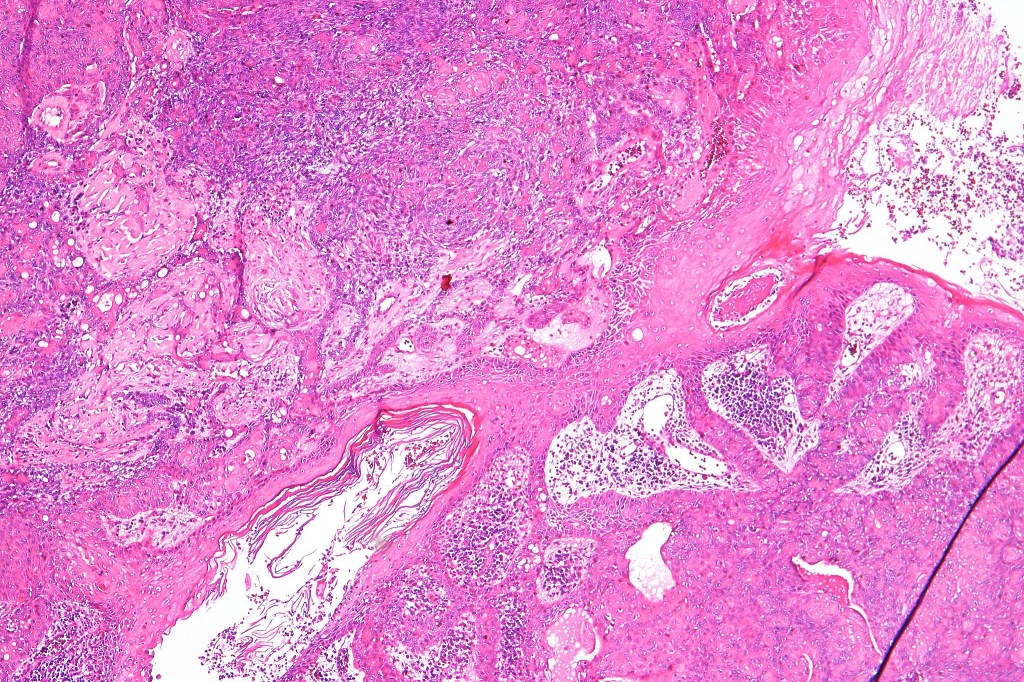

Histological features

•Variably derived from the acrosyringium, the dermal duct or both

•Dermal duct tumor comprises dermal nodules composed of poroid cells showing ductal differentiation & intracytoplasmic lumina with variable cyst formation

•In poroma, a dermal-centric tumor is associated with epidermal origin/continuity & is composed of small cells with vesical nuclei.

•No peripheral palisading or retraction artifact